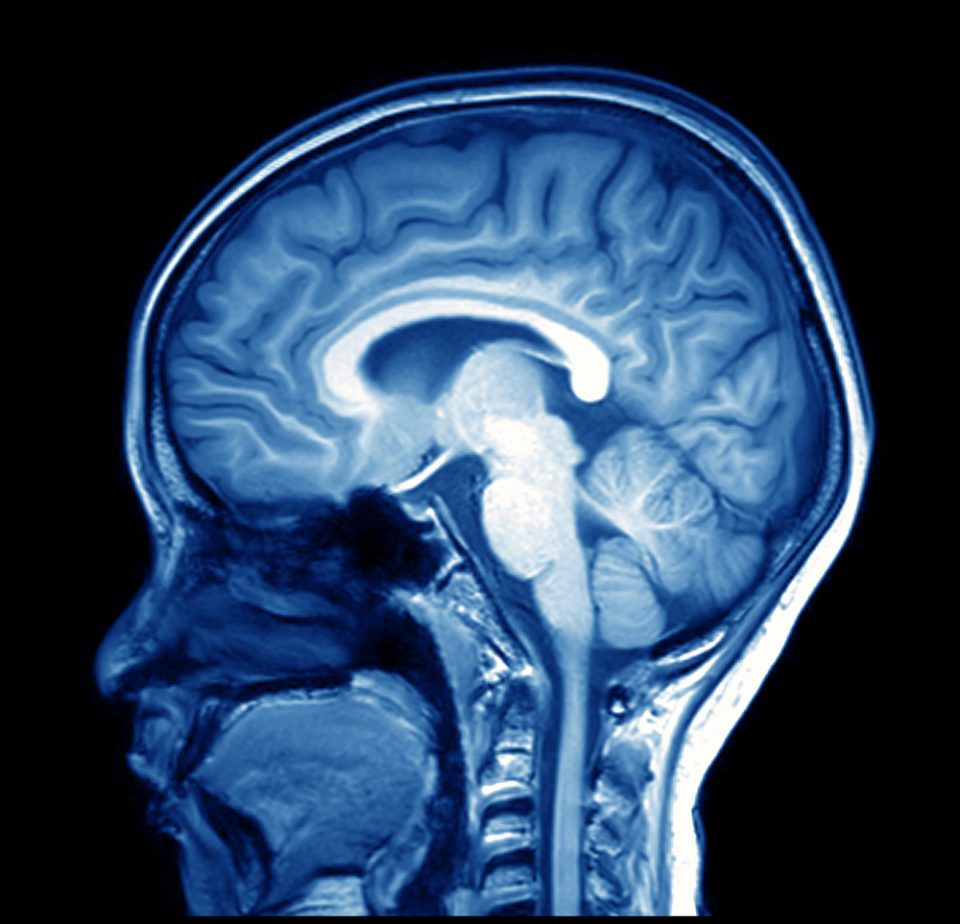

(MriMan/Shutterstock)

The study involved 70 independent research teams from around the world, who were all presented with the same data: functional magnetic resonance imaging (fMRI) scans of volunteers’ brains while they performed a monetary decision-making task.

The teams were told to test nine different hypotheses, but weren’t told how to do it. So each team devised its own methods for preparing the fMRI data for analysis, in addition to performing the actual analysis, which demanded a yes/no answer for whether the brain was activated for specific tasks.

The groups also set different thresholds for when parts of the brain were “activated” or not, which was a very important piece of data for the analysis, Hadhazy writes. “The teams could not even always agree on how to define anatomical regions of interest in the brain when applying statistical analysis,” he writes.

“The processing you have to go through from raw data to a result with fMRI is really complicated,” said paper co-senior author Russell Poldrack, according to Stanford News. “There are a lot of choices you have to make at each place in the analysis workflow.”